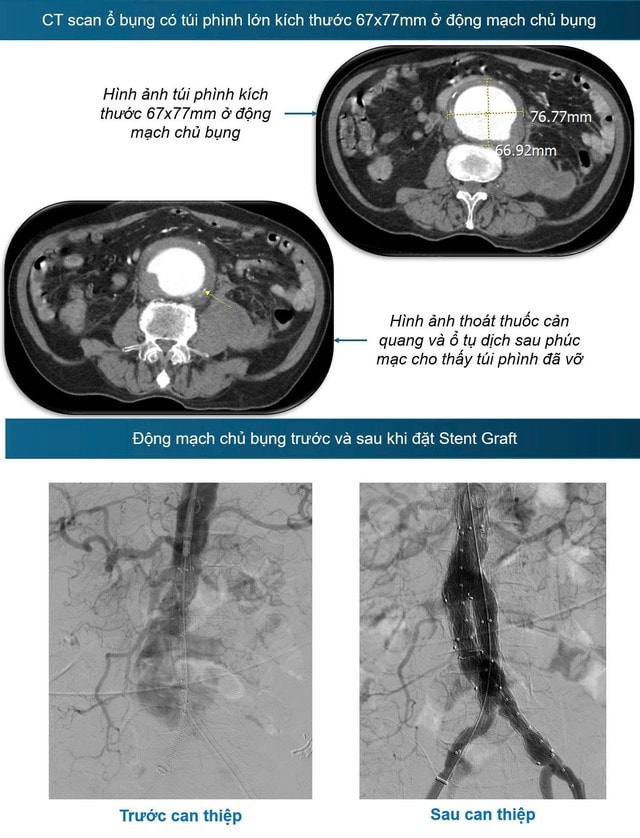

Bệnh nhân được chụp cắt lớp vi tính ổ bụng có thuốc và chẩn đoán vỡ túi phình hình thoi động mạch chủ bụng kích thước 6,7x7,7cm, gây chảy máu vào khoang sau phúc mạc – một tình trạng đe dọa tính mạng.

Trước tình huống nguy kịch, ê-kíp Tim mạch can thiệp đã nhanh chóng hội chẩn và ra quyết định can thiệp cấp cứu cho bệnh nhân. Song song với việc truyền máu và ổn định huyết động, bệnh nhân được tiến hành can thiệp nội mạch khẩn cấp. Kỹ thuật đặt stent graft đã được thực hiện nhanh chóng và thành công để bít kín vị trí vỡ động mạch chủ bụng.